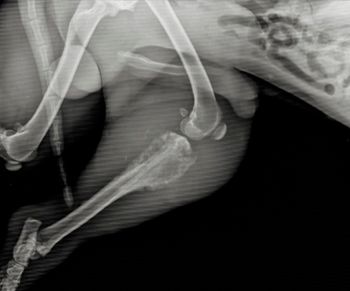

New laboratory tests allow veterinarians to screen their canine patients for the presence of cancer cells before the onset of clinical signs, which can improve patient outcomes.

May serve as future screening tool for diagnosis of canine cancer with potential to improve overall quality of life and lifespan of cancer patients

This new study demonstrates nucleosome concentrations are useful when treating canine cancer treatment monitoring